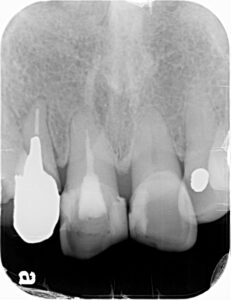

本日のインプラント症例は右上側切歯(2番目)です。レントゲンではわかりにくいですが破折していました。